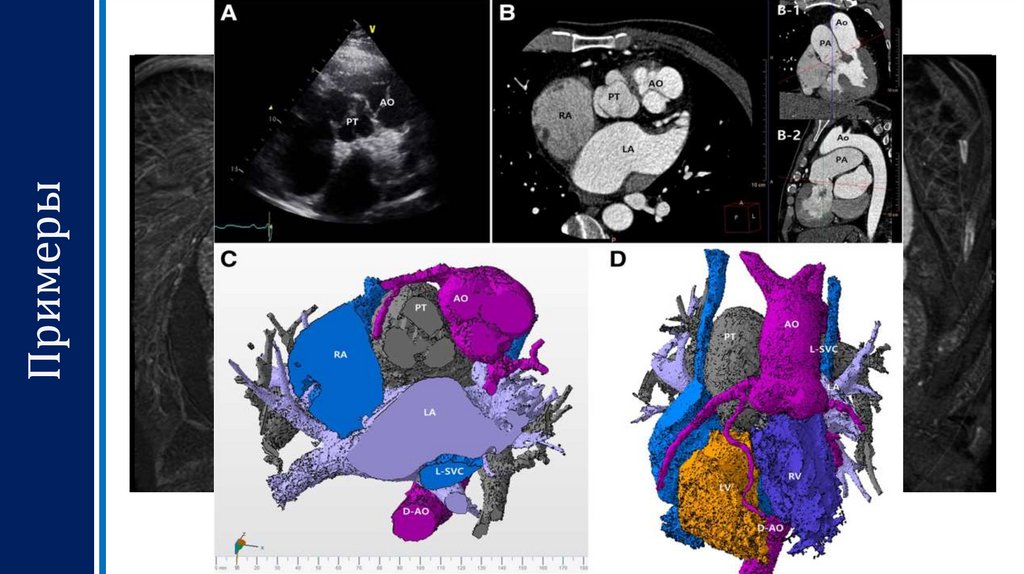

Примеры

7. Примеры